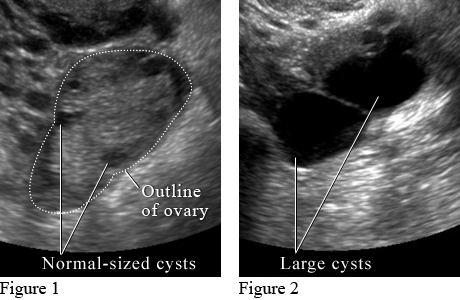

Ultrasound of Ovarian Cysts